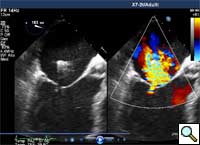

In absence of controlled clinical trial data which are forthcoming from the EVEREST II randomized study, the indications for the MitraClip therapy are currently based on registry experience and will evolve as the technique improves, experience is growing and the data to demonstrate efficacy and safety becomes available. At this time, the best indication for the MitraClip therapy is for symptomatic patients with clinically significant functional or degenerative MR who are at high or increased risk for open heart surgery. From a pure technical standpoint, the procedure so far has only been demonstrated in a subgroup of patients with specific anatomical characteristics which are summarized below and shown in Figure 3. Anatomic suitability is assessed by transesophageal echocardiography, and mitral regurgitation should originate from the central portion of the valve involving the A2-P2 segments, since the device is not ideal to work in the commissures at this time; the mechanism of MR can be either a prolapse/flail or MR due to restricted leaflet motion unrelated to rheumatic disease; the separation between the two leaflets at the site of regurgitation should be limited; severe annular dilatation and/or severe calcification should be absent or is relevant. In case of flail, the flail segment width should be less than 15 mm, and the flail gap less than 10 mm. Figure 4 is a 3D echo image of a patient with posterior leaflet prolapse selected for MitraClip therapy. In case of functional MR, the leaflets should have a minimal residual tissue available for coaptation with the MitraClip device. Figure 5 shows 2D color Doppler jet extension over the coaptation line at TEE short axis transgastric view, while Figure 6 shows the tenting area and the coaptation depth of a patient undergoing MitraClip implant.